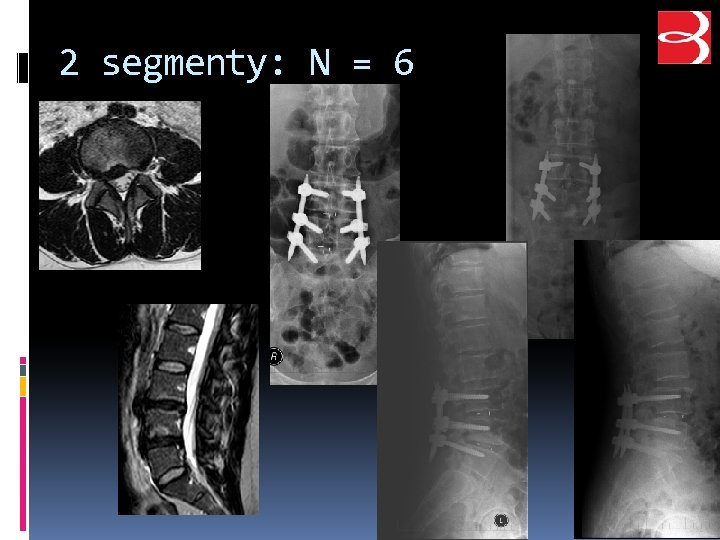

2 segmenty: N = 6